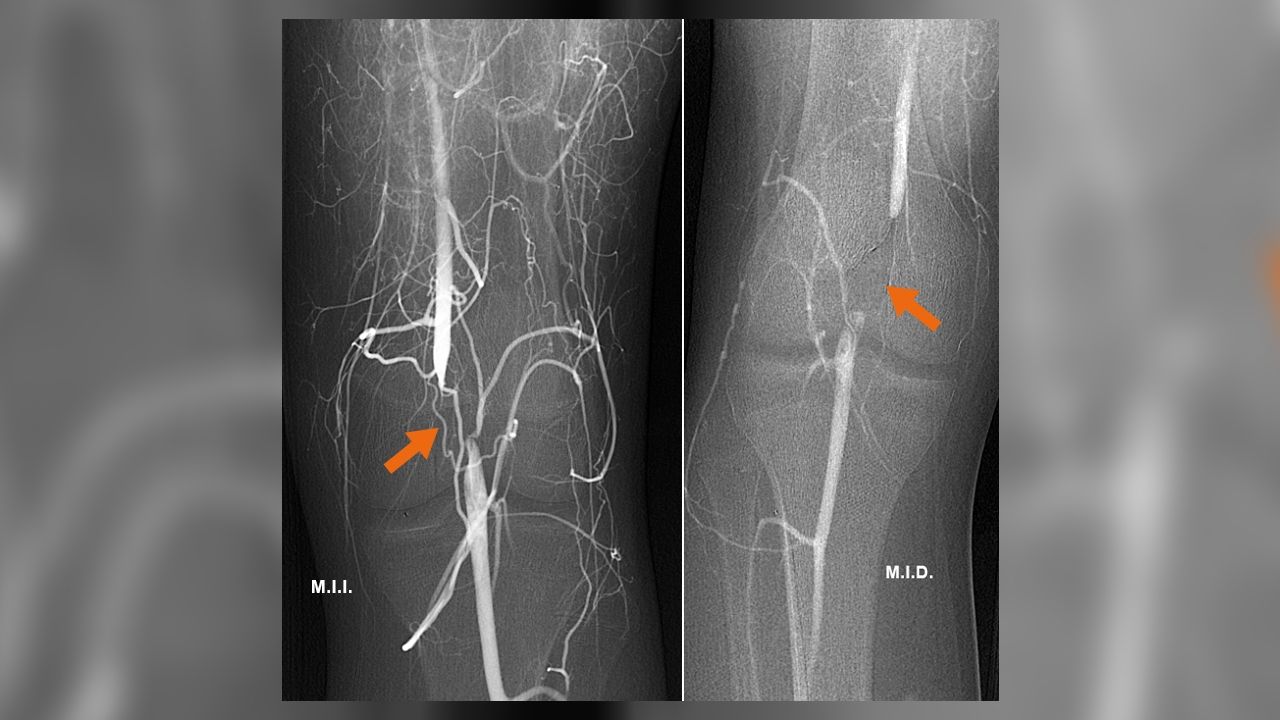

Cuando el diagnóstico está establecido, la flebografía pélvica (iliocavografía) pasa a ser el siguiente escalón en el proceso. “Una técnica mediante punción de una vena del brazo y pasando un catéter guiado por rayos X en una sala de angiografía digital para realizar estudios selectivos de las venas pélvicas con toma de presiones para valorar las posibles compresiones, así como visualizar las varices pélvicas. En el mismo acto, se realiza el tratamiento endovascular ocluyendo los reflujos mediante coils para combatir la congestión pélvica (varices) o incluso dilatando mediante implante de un stent en los casos secundarios a síndromes compresivos. Estos dos procedimientos, embolización e implante de stent, normalizan la circulación venosa de la pelvis y del abdomen combatiendo las varices pélvicas que originan el cuadro doloroso”, asevera el doctor Santiago Zubicoa Ezpeleta, responsable de la Unidad de Radiología Vascular Intervencionista.